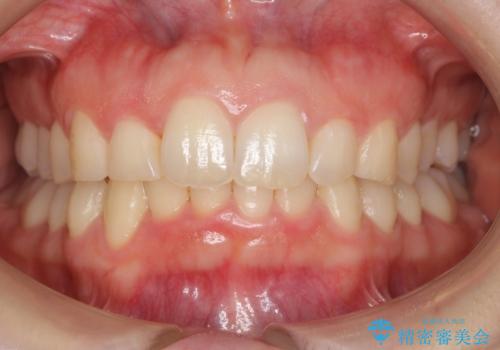

抜かない矯正 前歯がとび出ているのをマウスピースで

遠心移動などは行わず、IPRと拡大のみで治療を行いました。

一般的に非抜歯矯正を無理に行うと、口元がモッコリ出てしまうことがあります。しかし、今回は前歯を前に出さないような設定にしており、口元が出ることもありませんでした。